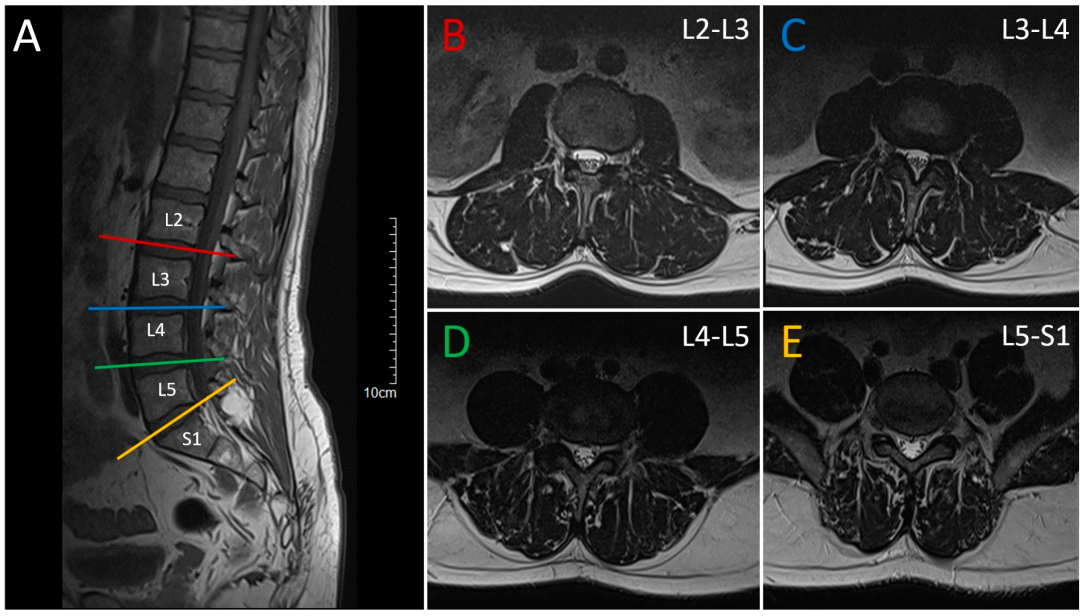

2. Case Presentation